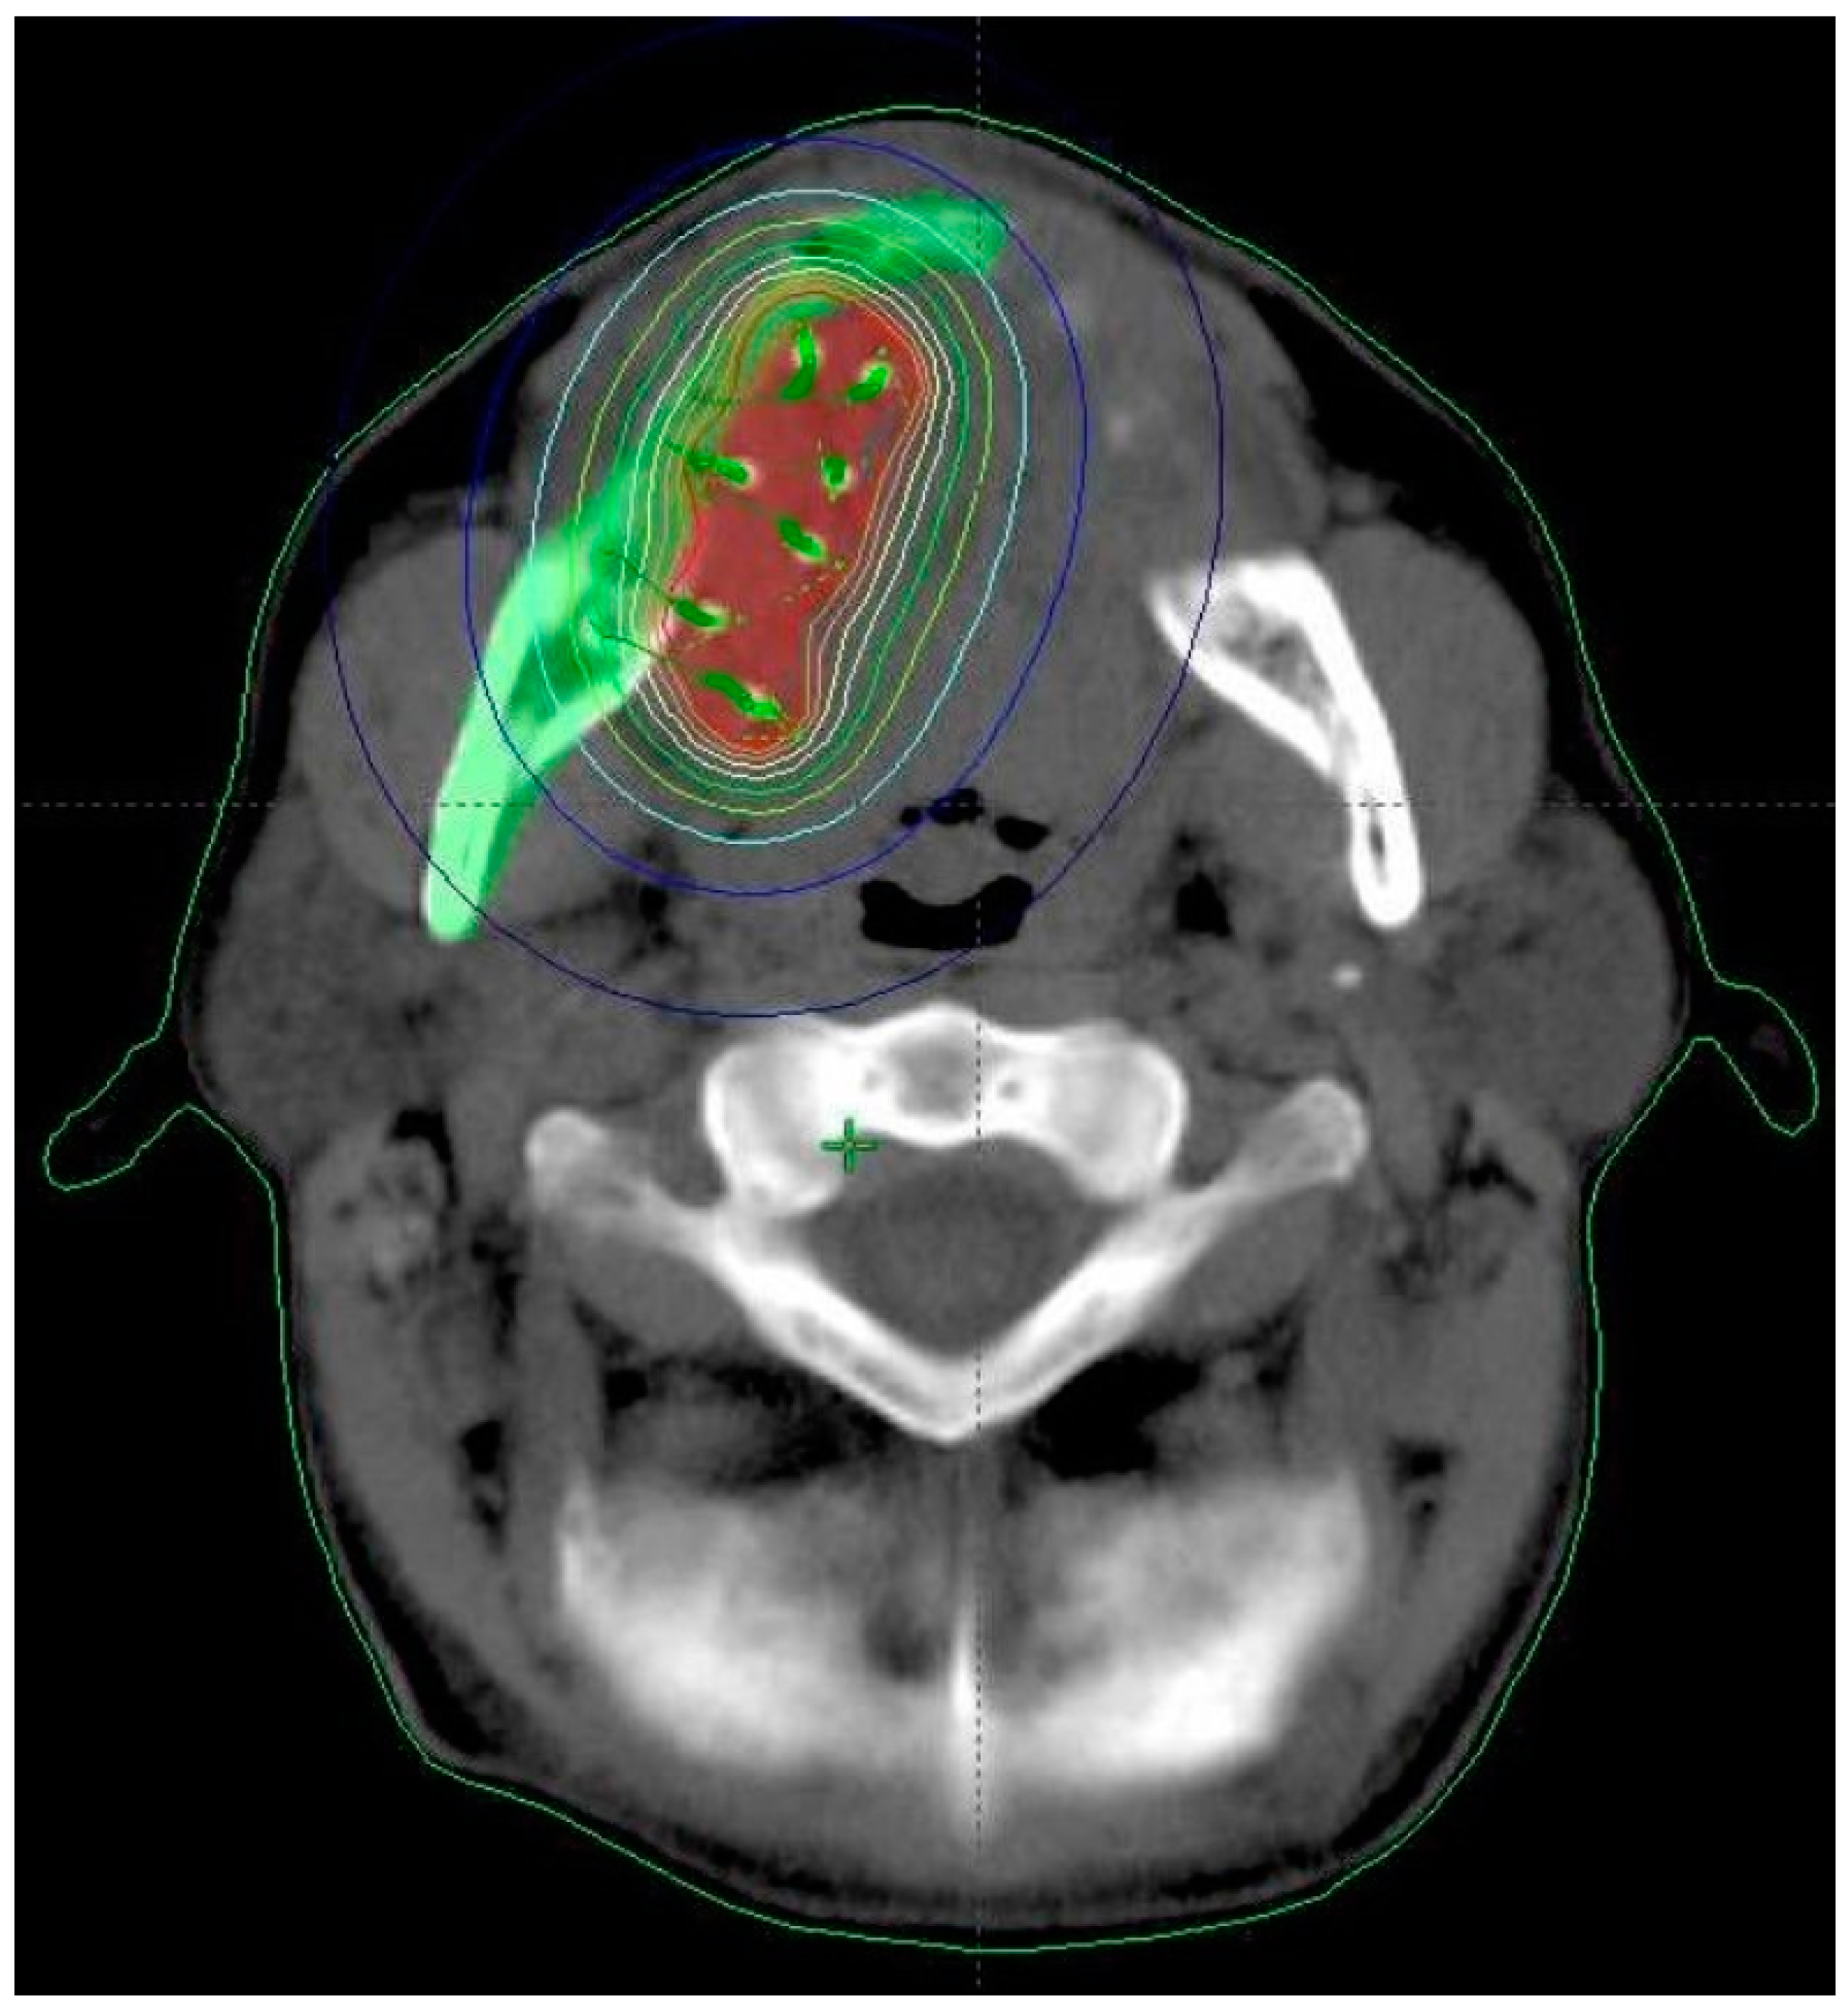

- Kovács, G.; Martinez-Monge, R.; Budrukkar, A.; Guinot, J.L.; Johansson, B.; Strnad, V.; Skowronek, J.; Rovirosa, A.; Siebert, F.A.; GEC-ESTRO Head & Neck Working Group. GEC-ESTRO ACROP recommendations for head & neck brachytherapy in squamous cell carcinomas: 1st update—Improvement by cross sectional imaging based treatment planning and stepping source technology. Radiother. Oncol. 2017, 122, 248–254. [Google Scholar] [CrossRef] [PubMed]

- García-Consuegra, A.; Gimeno Morales, M.; Cambeiro, M.; Tagliaferri, L.; Kovacs, G.; Van Limbergen, E.; Ramos, L.I.; Manuel Arnaiz, J.; Alcalde, J.; Lecanda, F.; et al. Dose volume histogram constraints in patients with head and neck cancer treated with surgery and adjuvant HDR brachytherapy: A proposal of the head and neck and skin GEC ESTRO Working group. Radiother. Oncol. 2021, 154, 128–134. [Google Scholar] [CrossRef] [PubMed]